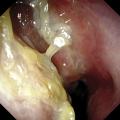

Polypose nasosinusienne

La polypose nasosinusienne est une rhinosinusite diffuse caractérisée par la présence de polypes bilatéraux dans les cavités nasales venant du massif ethmoïdal. Sa physiopathologie repose sur une inflammation chronique de la muqueuse des cavités nasales et sinusiennes marquée par une infiltration éosinophilique plus ou moins…

Tableaux et figures